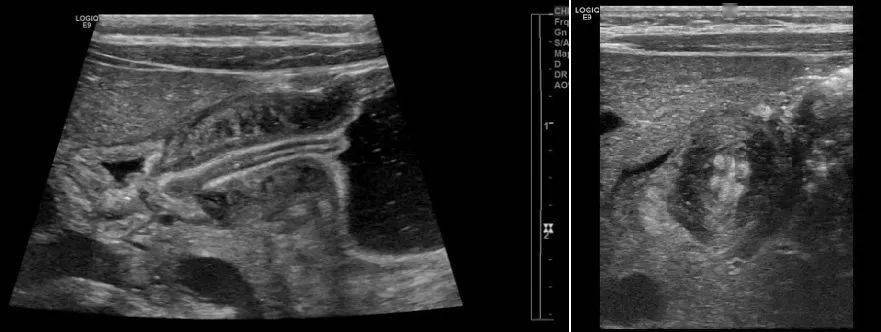

先天性肥厚性幽门狭窄--图片

图片尺寸801x561![【共享】先天性幽门肥厚的上消化道造影表现小结 [病例帖]](https://i.ecywang.com/upload/1/img2.baidu.com/it/u=835988170,3580433256&fm=253&fmt=auto&app=138&f=JPEG?w=250&h=500)